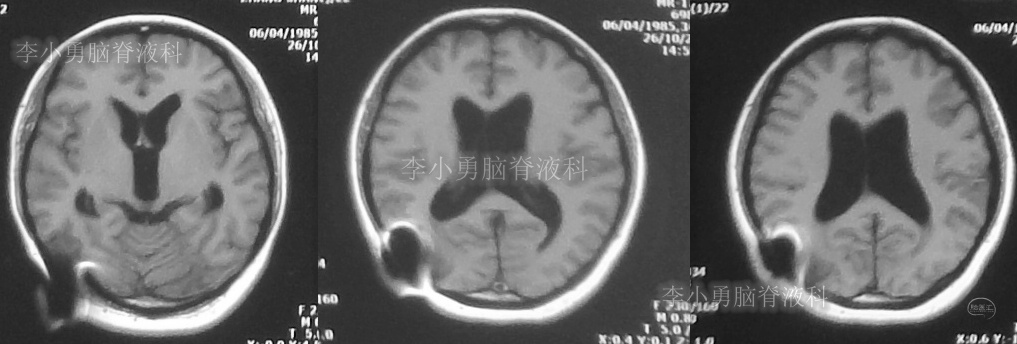

又2天后,即2018年2月5日,为求更好的治疗,患者转到第2家医院:浙江省杭州市的某三甲医院就诊,行头颅增强核磁共振检查(图-2)提示双侧脑室及第三脑室扩张,中脑导水管形态消失,第四脑室无扩张,未见颅内占位病变。

图-2:2018年2月5日头颅核磁